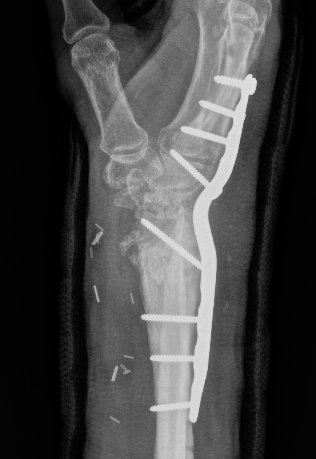

Flexor tendon rupture

Etiology

Plates distal to watershed mark

Prominent screws

Thicker plates

Incidence

Asadollahi et al J Orthop Traumatol 2013

- systematic review of flexor tendon rupture after plating of distal radius fractures

- 47 cases

- FPL 57%

- FDP to index finger 15%

Volar rim plates

Lari et al Eur J Orthop Surg Traumatol 2023

- systematic review of surgical treatment of volar rim fractures

- 26 studies and 600 patients

- implant removal 22%

- flexor tendon irritation 6%